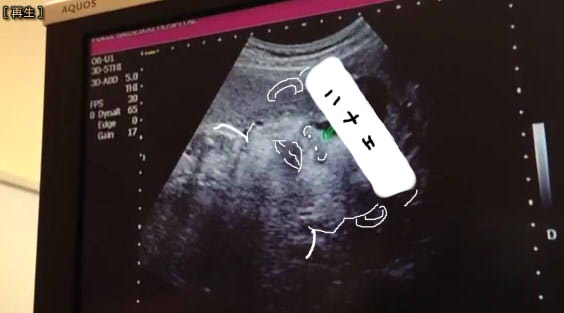

横、、、!横見せてくれ、、、!!

ただの俊也把握。

めっちゃ俊也さんやんけ!!!!!!!!!!!!!!!!!